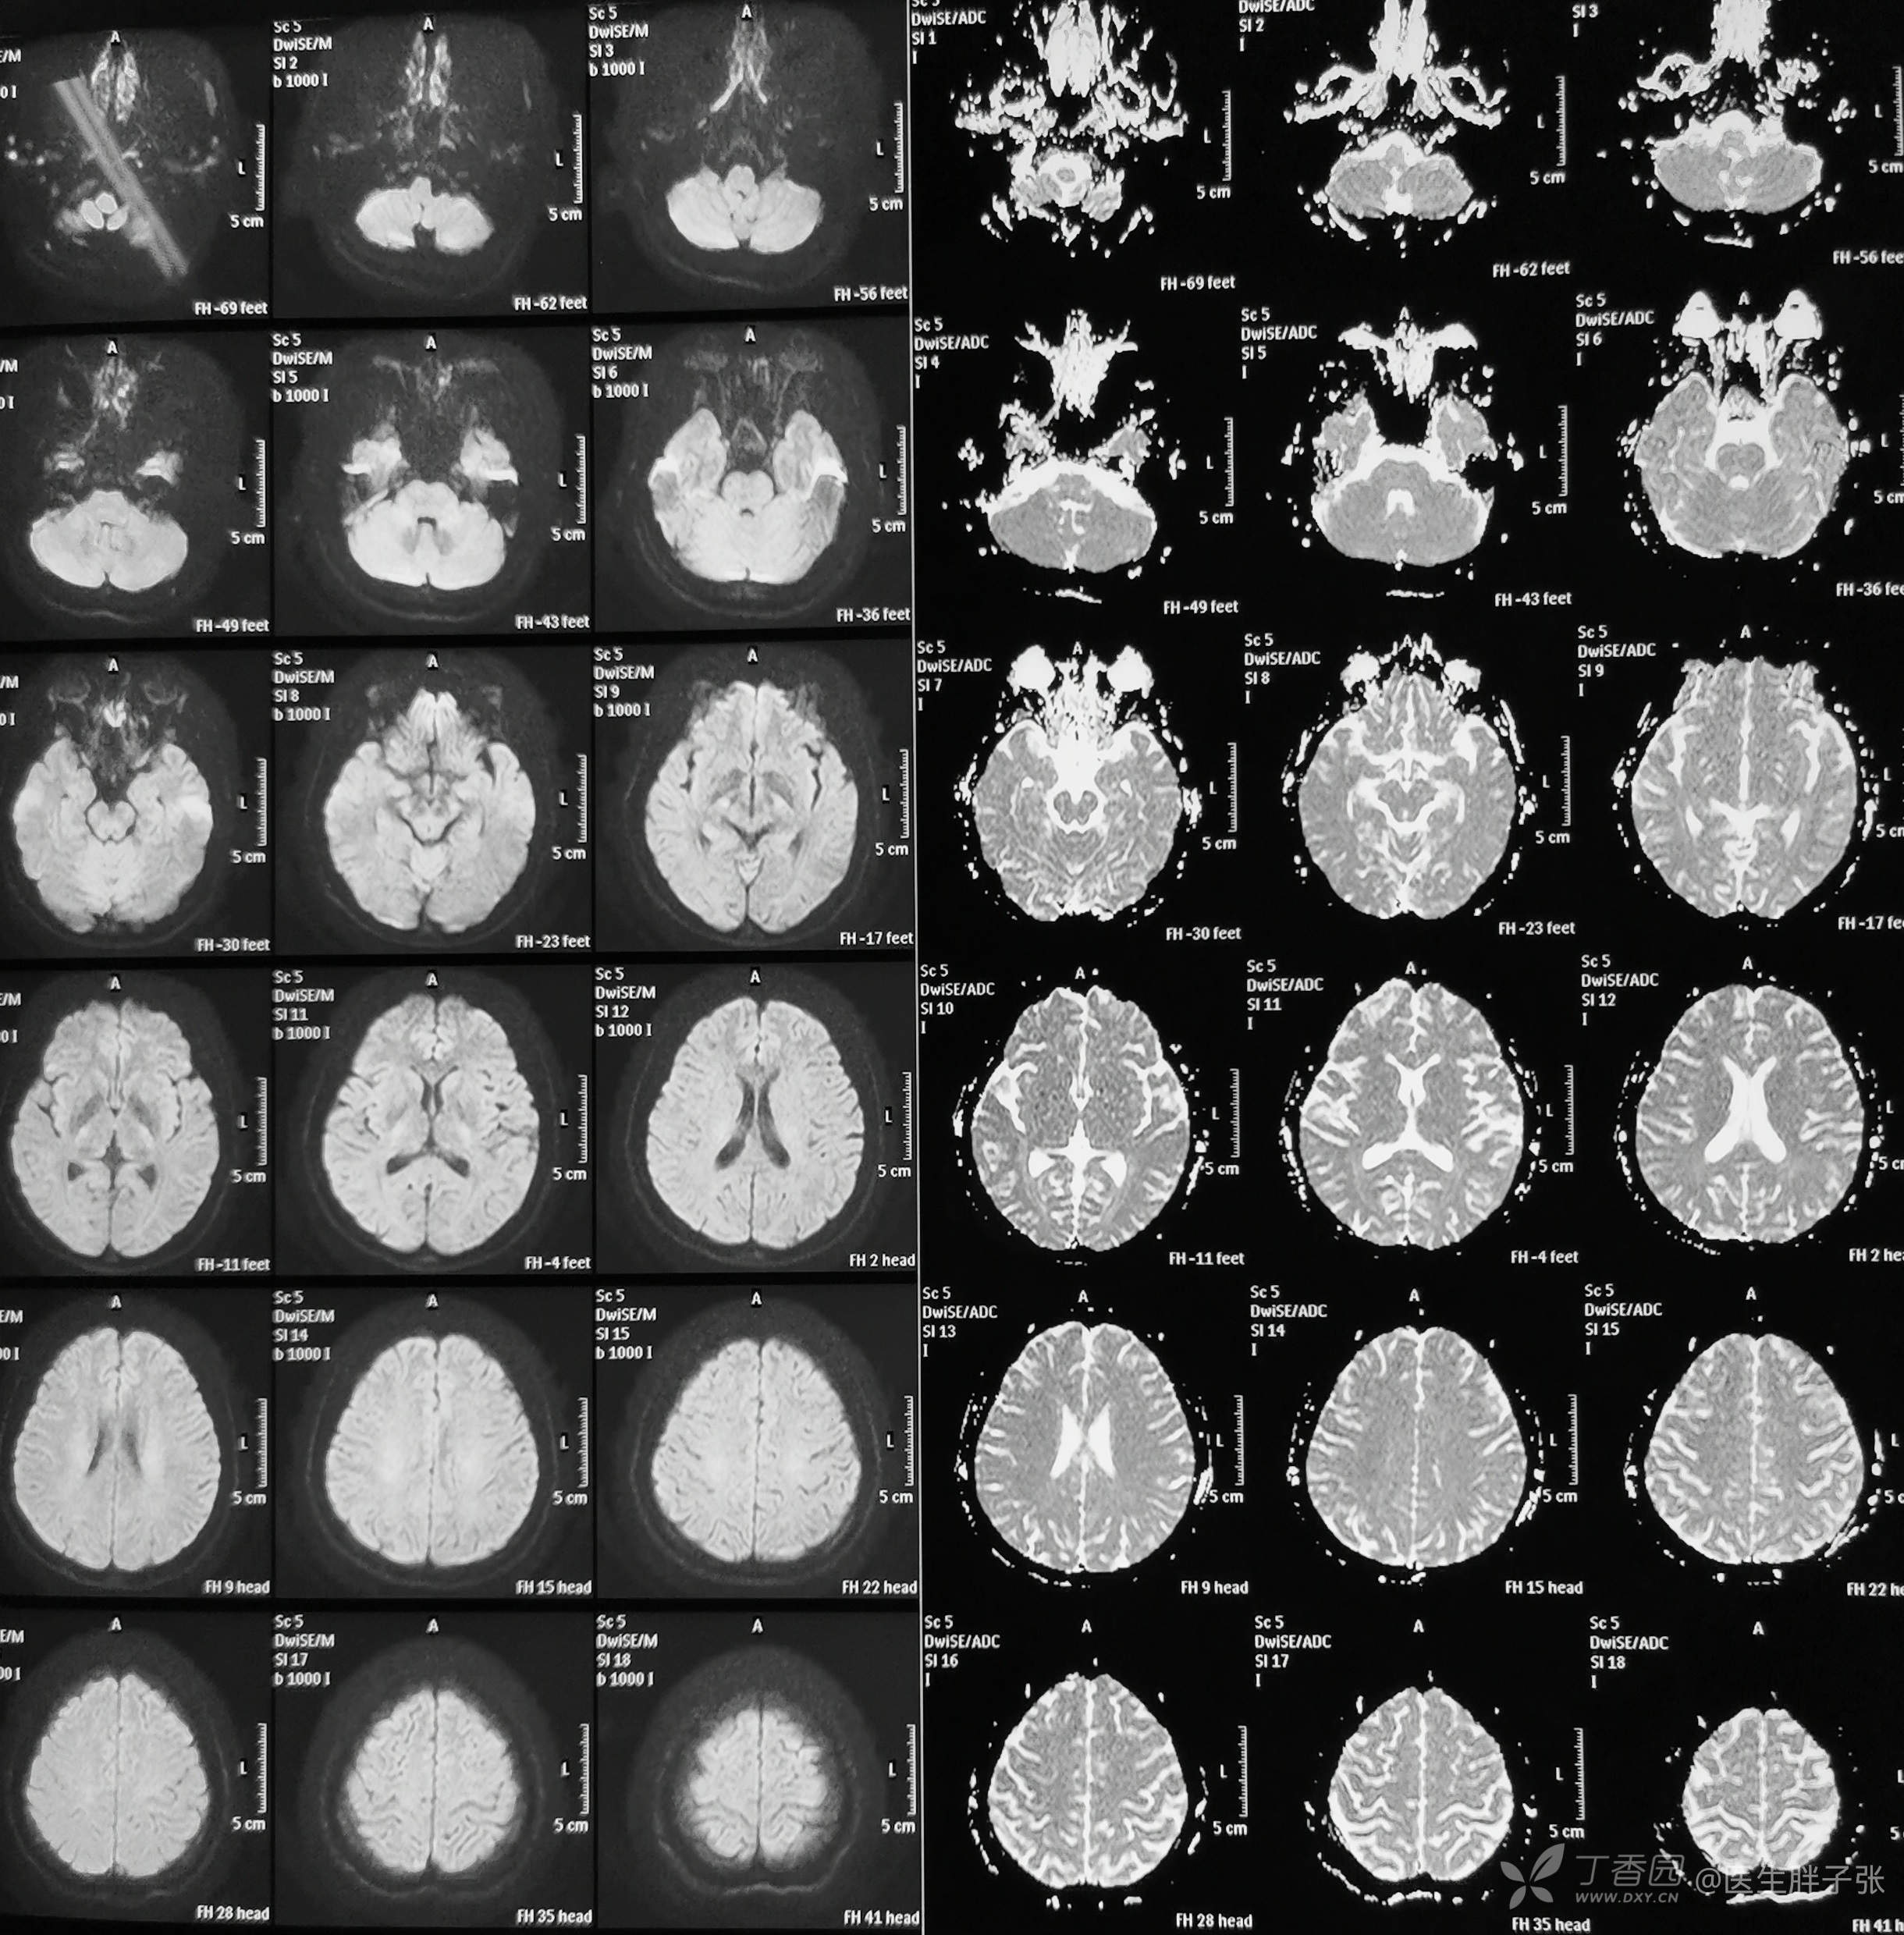

辅助检查:心电图示冠状静脉窦心率,V4、V5 T波改变。颅脑核磁:MRI平扫及MRA未见异常。右侧横窦、上矢状窦局部官腔充盈缺损,考虑静脉窦血栓可能性大,直窦、下矢状窦未见显示,先天发育异常可能性大。